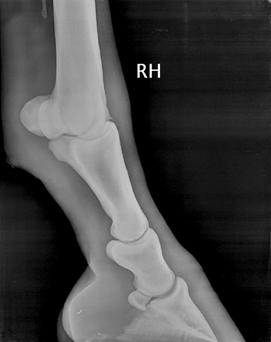

Kulno sąnario OCD (13 pav.) pasireiškia keliose skirtingose sąnario vietose: blauzdikaulio intermedialinėje keteroje, kulno distaliniame lateraliniame skridinyje, rečiau – blauzdikaulio plaktukėliuose ir kulno medialiniame skridinyje (Ross M.W., Dyson S.J., 2003, Bramlage L.R., 2006).

Diagnozuojant ligą, daromos 4 standartinės kulno sąnario rentgenogramos. Tai: dorsoplantarinė, lateromedialinė ir 2 įstrižos projekcijos. Iš jų dorsolateralinė ar dorsoplantarinė mediolateralinė įstrižos projekcijos suteikia daugiausiai informacijos (Ross M.W., Dyson S., 2003, Bramlage L.R., 2006).

13 pav. a) Medialinė įstriža kulnakaulio projekcija. b) Lateralinė kulnakaulio projekcija (cal.vet.upenn.edu ).